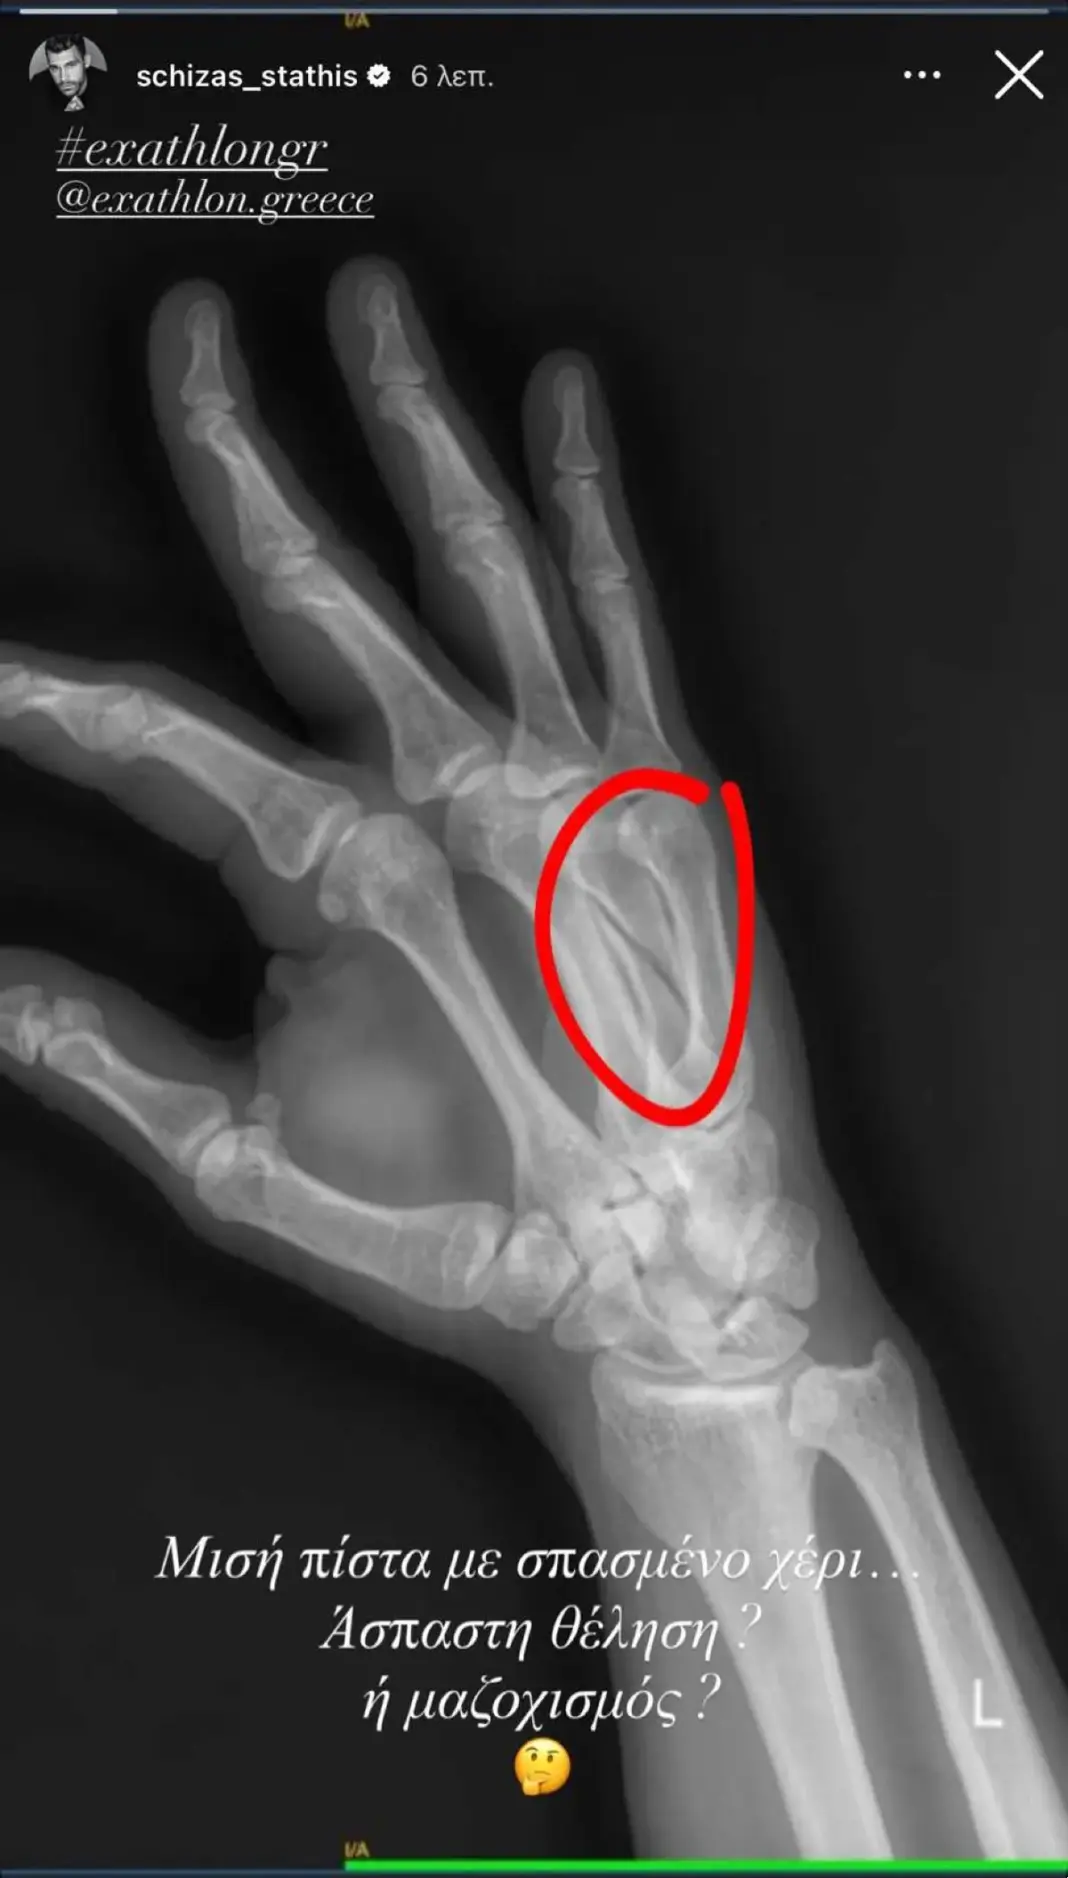

Δημοσίευσε στο Instagram μια φωτογραφία της ακτινογραφίας του, δείχνοντας το κάταγμα και σχολιάζοντας με χιούμορ την κατάσταση.

Όπως βλέπουμε από τα χθεσινά πλάνα, την ώρα που έπαιζε ενάντια στον Άρη Σοϊλέδη, χτύπησε με πολύ δύναμη στο χέρι του και αφού έκανε τις απαραίτητες εξετάσεις, αποκαλύφθηκε πως έπαθε κάταγμα – δείτε εδώ το βίντεο -, γι’ αυτό και χρειάστηκε να αποχωρήσει από το παιχνίδι. Μετά την προβολή του επεισοδίου, ο Στάθης Σχίζας έκανε μία ανάρτηση στον προσωπικό του λογαριασμό στο Instagram, δημοσιεύοντας μία φωτογραφία από την ακτινογραφία του, όπου φαίνεται ξεκάθαρα το κάταγμα και έγραψε: «Μισή πίστα με σπασμένο χέρι… Άσπαστη θέληση ή μαζοχισμός;».